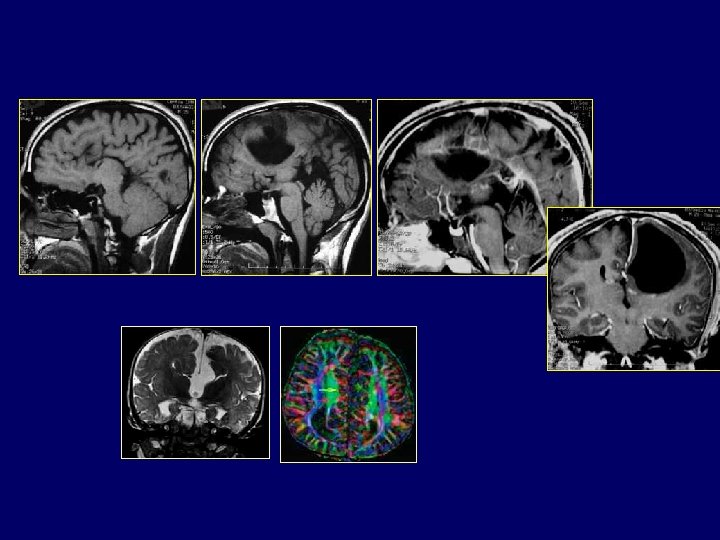

Holoprosencéphalie alobaire • Vésicule cérébrale unique, non segmentée en lobes avec ventricule unique • Absence de bulbe olfactif • Absence de massif facial médian: induit la diverticulation • Nerf et cupule optique impairs • Absence ou insuffisance hypophysaire avec fusion thalamique (absence d’hypothalamus) • Fusion thalamique inconstante • Malformation rare : 1 NNé / 20. 000 • Défaut de clivage médian du cerveau avec : >Cyclopisme >>>> fentes palatines et/ou labiales >Microcéphalie >>>>hypothélorisme oculaire

Holoprosencéphalie lobaire • Lobes cérébraux bien développés mais sans septum • Plancher ventriculaire commun • Face normale • Forme mineure: Dysplasie septo-optique de De Morsier: atrophie optique, ventricule unique et insuffisance hypophysaire. Holoprosencéphalie intermédiaire • Ventricule unique • Développement imparfait des lobes cérébraux

AGENESIE COMMISSURALES • Formes communes : – Agénésie complète : CA, CC, CH – Agénésie partielle : simple, particulière. – Formes kystiques • Formes plus rares

AGENESIE COMPLETE • Absence de tous les éléments de la plaque commissurale : – CA – CC – CH – 33 % des agénésies, la plus typique (100 cas) • VL séparés de la ligne médiane • Scissure inter hémisphérique arrivant au toit du V 3 expansion du toit sur un coté jusqu’à la voûte

• Absence de gyrus cingulaire : sillons à trajet radiaire vers la paroi ventriculaire • VL limité en médial par une lame de SB – Niveau thalamique : du cortex septal à la fimbria fornix longitudinal – Plus haut : lame épaissie contenant les fibres calleuses bande de Probst • Aspect particulier en cornes de bœuf des VL Empreinte des bandes de Probst sur les VL • Aspect particulier des cornes temporales.

AGENESIE COMPLETE • Anomalies associées : – Hétérotopie 5/33 – Cérébelleuse 3/33 : • agénésie vermienne, • malformation DW – Visuelles 7/33 : • Colobome, microphtalmie • Nystagmus congénital – Défects facial et crâniens 8/33 : • Fente labiale • Encéphalocéle – Autres : hypophyse (2), rachis (2), cœur (2), extrémités (2) – Clinique : épilepsie et RPM 18/33, 2 N uniquement. Raybaud et Girard, International pediatric radiology Post – Graduate course, Paris Mai 2001

AGENESIE PARTIELLE • 30 % des agénésies • Agénésie partielle simple : – Partie manquante (POST) – Reste normal – Même aspect que pour les formes complètes • Agénésie particulière : – – Épaisseur normale Partie postérieure effilée Commissure courte Cerveau de morphologie normale Mêmes types de lésions associées et même fréquence (2 N) Raybaud et Girard, International pediatric radiology Post – Graduate course, Paris Mai 2001

FORMES KYSTIQUES • Forme habituelle : – ESA normaux – Maximum : expansion dorsale du toit du V 3 • Formes kystiques : – 13 % Kystes non communiquant avec les ventricules souvent multiloculaires – CA présente, le reste manquant totalement ou en partie – Aspect du cerveau difficile à analyser de part la distorsion crée par le kyste – Cortex bordant le kyste est dysplasique – hétérotopie fréquente • Clinique : macrocéphalie isolée, parfois dans un syndrome d’AICARDI

FORMES RARES • Nécessitent une analyse morphologique et anatomique très précise • Agénésie : – CA (3 %) évidente en sagittal – CC (11 % ) • complète 3 % : CH existe au dessus du toit du V 3 • Partielle 8 % : processus destructif incriminé – CH (6 %) : diagnostic de cavum pellucidum persistant Cependant l’absence de fornix et de CH interposés entre CC et toit du V 3 permet le diagnostic.